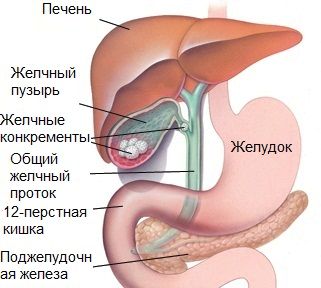

Жовчнокам'яна хвороба (ЖКХ) - це стан організму, яке супроводжується утворенням каменів в жовчному міхурі і жовчних протоках.

жовчні камені - Це щільні утворення, по вигляду нагадують камінь і утворюються при осадженні нерозчинних компонентів жовчі: холестерину, кальцію, білірубіну.